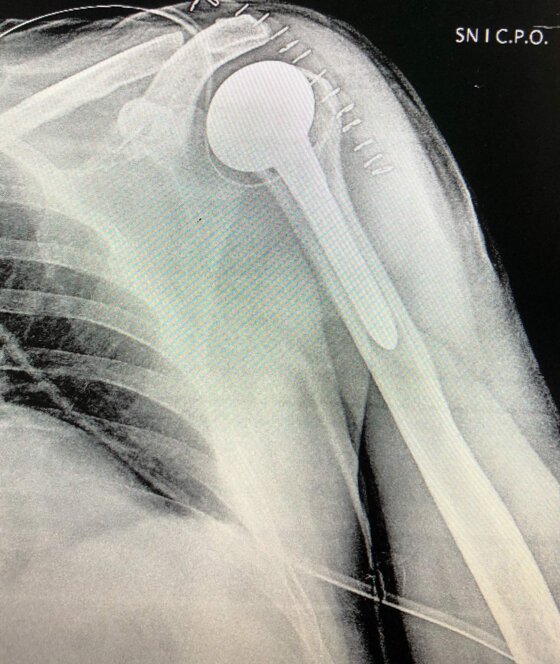

A destra radiografia post-operatoria di intervento chirurgico di protesi inversa spalla effettuato in pz con artrosi e rottura massiva cuffia dei rotatori.

Il trattamento nelle fasi iniziali si avvale di farmaci anti-infiammatori e terapia fisica per il controllo del dolore, riabilitazione per il mantenimento del tono muscolare e della mobilità articolare. Utili le infiltrazioni con acido ialuronico e la medicina rigenerativa (infiltrazioni o con PRP o cellule mesenchimali prelevate dal tessuto adiposo). Nelle fasi avanzate il trattamento indicato è l’intervento chirurgico di Protesi di spalla. Nell’ artrosi concentrica si utilizzano protesi o solo omerale o totale secondo lo stato della cavità glenoide. Nell’artrosi da rottura della cuffia si utililizza la Protesi Inversa che consente la mobilità attiva della spalla anche in assenza dei tendini della cuffia dei rotatori. Dopo la sostituzione protesica è necessario un intenso e prolungato percorso di fisiochinesiterapia.